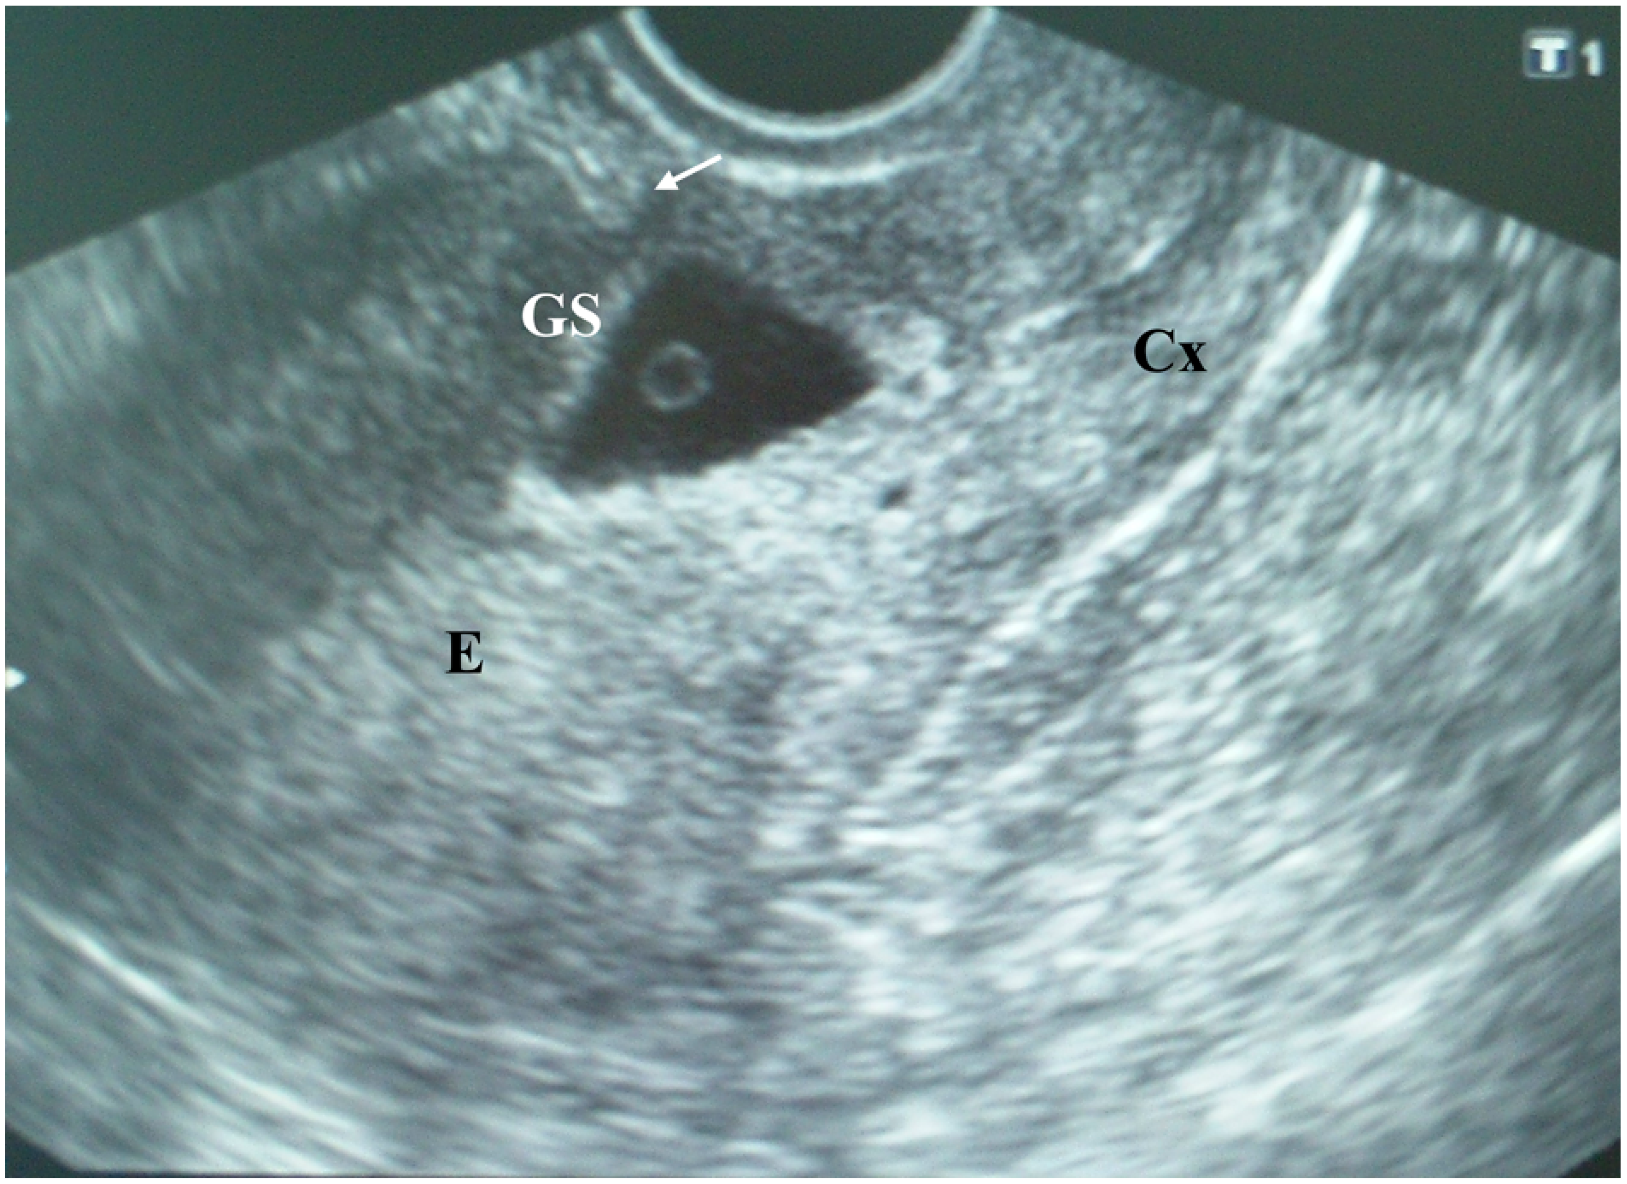

On admission, the patient was hemodynamically stable. An examination of her cardiac and respiratory systems was unremarkable. Her abdomen was soft without tenderness. A speculum examination indicated the presence of a single cervix with brown-colored discharge from the external os and no other pathological findings. Bimanual pelvic examination revealed an enlarged soft uterus corresponding to the sixth gestational week; the patient’s cervix was closed with no pathological adnexal findings. Transvaginal ultrasound examination (TVUS) [Toshiba Nemio XG, 6 MHz] showed an empty uterine cavity with a 9 mm endometrial strip and a triangular gestational sac (10 mm in diameter) located within the isthmic part of the anterior uterine wall that filled the niche of the scar, with a yolk sac inside (Figure 1). Both ovaries appeared sonographically normal, with a corpus luteum on the left ovary. There was no intraperitoneal fluid in the pouch of Douglas. A color Doppler ultrasound image of the cesarean scar gestational sac showed peripheral hypervascularity.

Figure 1.

Transvaginal ultrasound examination of a cesarean scar pregnancy (CSP) at the sixth postmenstrual week showing an empty uterine cavity with a 9 mm endometrial strip (E) and a triangular gestational sac (10 mm in diameter) located within the isthmic part of the anterior uterine wall filling the niche of the scar, with a yolk sac inside covered with a thin myometrial layer 2 mm in diameter (arrow); the cervical channel (Cx) is empty; according to the presence of cross over sign (COS), this gestational sac could be identified as COS-1; according to the implantation of the gestation sac it is implanted in the niche of the scar (ultrasound sign reported by Kaelin Agten et al.); according to the position of the center of the gestational sac it could be classified as implantation bellow the uterine midline (classification proposed by Timor-Tritsch et al.) (explanation in Discussion).

Another ultrasound grading system for cesarean scar pregnancy has been recently developed based on the location of the gestational sac and the amount of myometrium remaining [15]. Grade I CSP is defined as the gestational sac penetrating less than half of the myometrium, whereas grade II CSP is defined as penetration greater than a half the myometrium. In grade III CSP gestational sac develops outside the myometrium. In grade IV CSP, the pregnancy is difficult to identify; the gestational sac is highly vascular. According to the first ultrasound examination (Figure 1), the CSP of our patient could be classified as grade II.